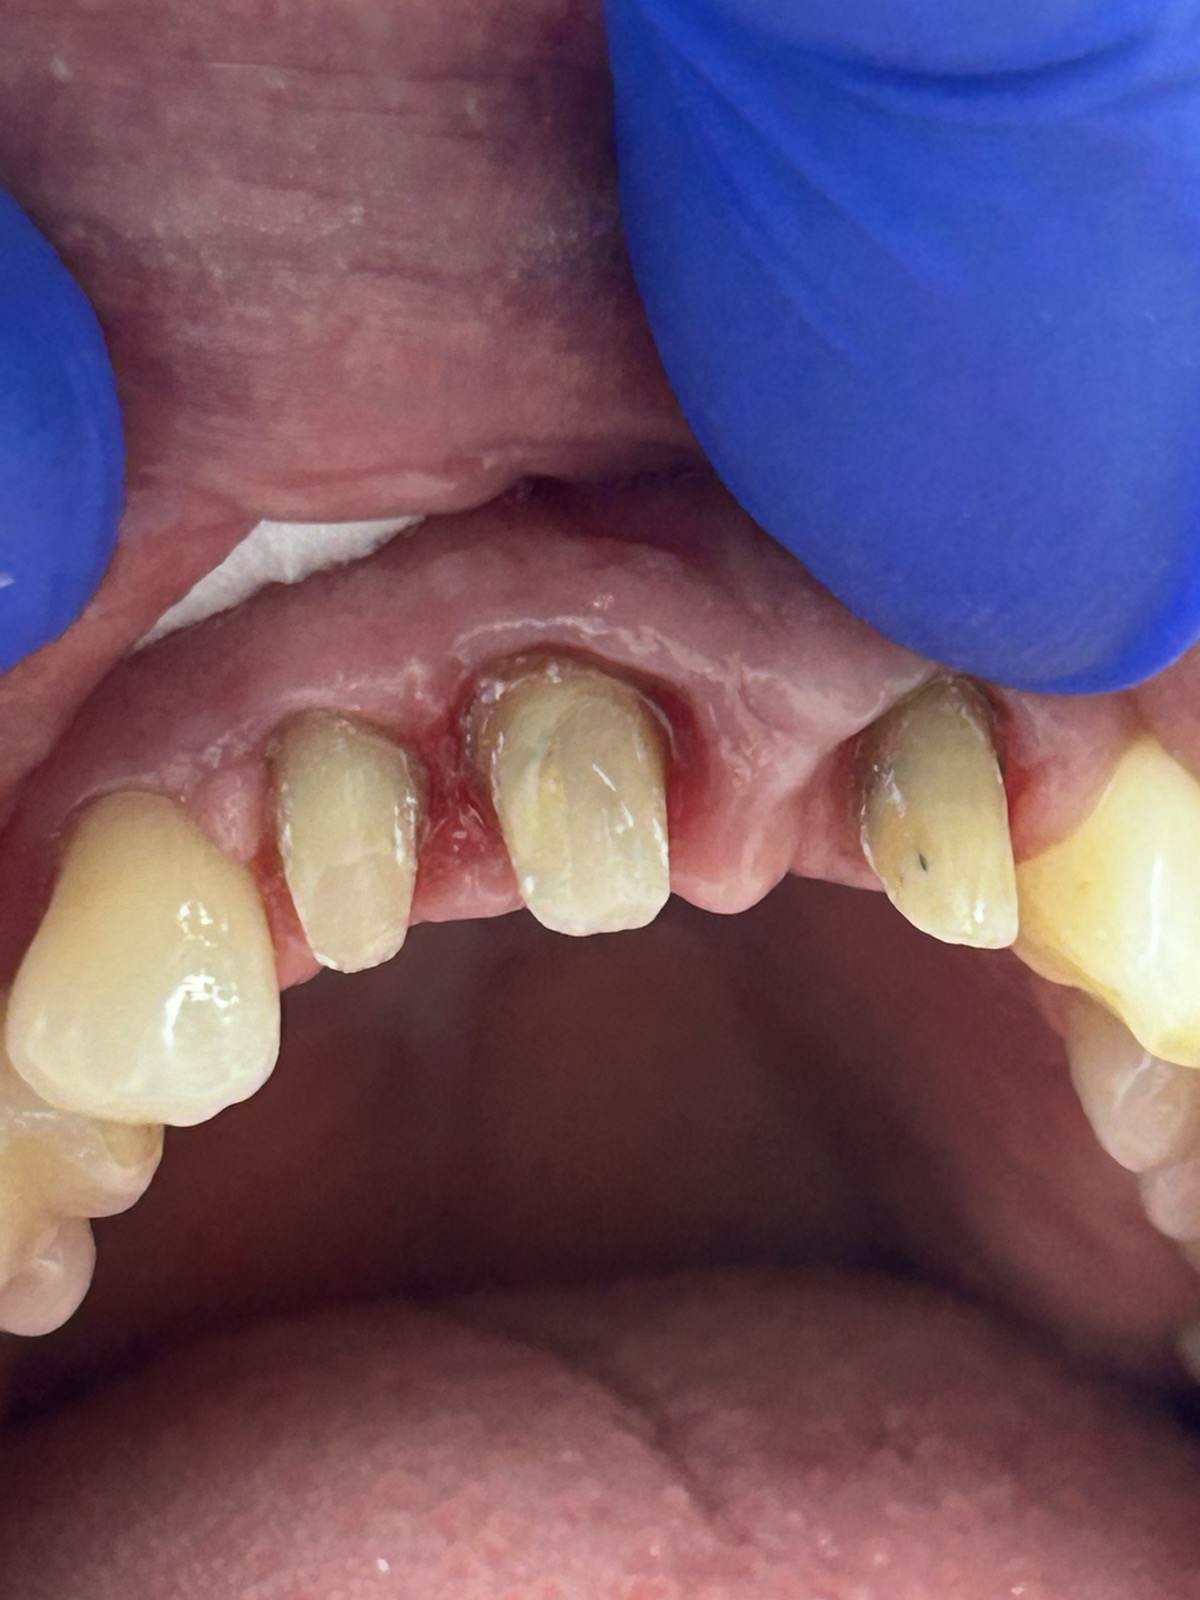

Пациентка обратилась с жалобами на нарушение эстетики ( потемнение) зубов 1.1, 1.2, 2.1. Зубы депульпированы 6 лет назад.

Пациентке предложено протезирование зубов коронками из диоксида циркония.